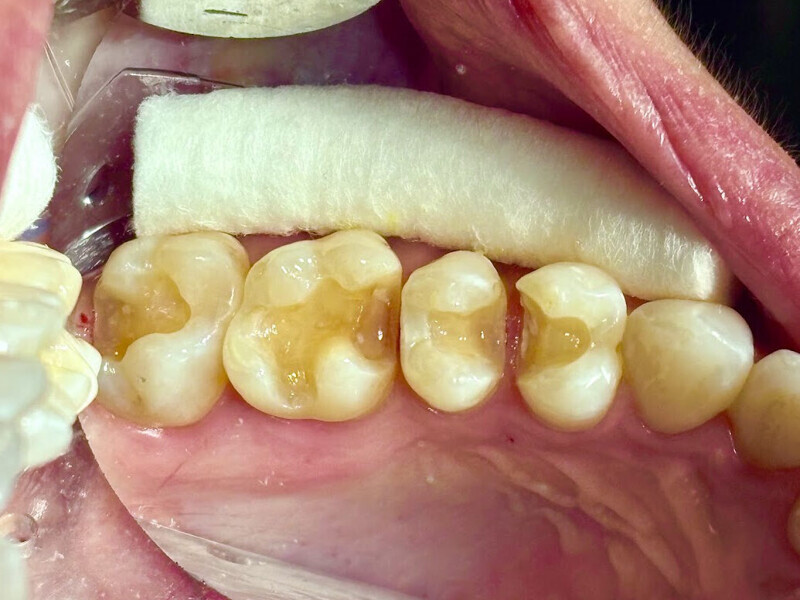

Fig. 19: Clinical view of the old composite restorations with recurrent caries on the molars and premolars.

A 23-year-old female patient presented with cold sensitivity of the teeth in the maxillary right posterior sextant. Examination noted old composite fillings in the molars and premolars and recurrent caries on each tooth (Fig. 19). A bitewing radiograph was taken to evaluate the extent of the recurrent caries and the dimensions of the composite restorations (Fig. 20). Owing to the dimensions of the restorations and caries, inlay and onlay restorations were suggested to restore the teeth and preserve tooth structure as an alternative to complete crowns. The patient’s questions were answered, and she agreed to the proposed treatment. She was informed that the treatment could be completed in a single appointment utilising 3D printing for restoration fabrication. Time in the schedule permitted treatment to be performed during that same appointment. Our intent is to provide conservative restoration with superior accuracy and definition compared with milling, as well as better predictability and mechanical properties compared with direct resin composite restorations.